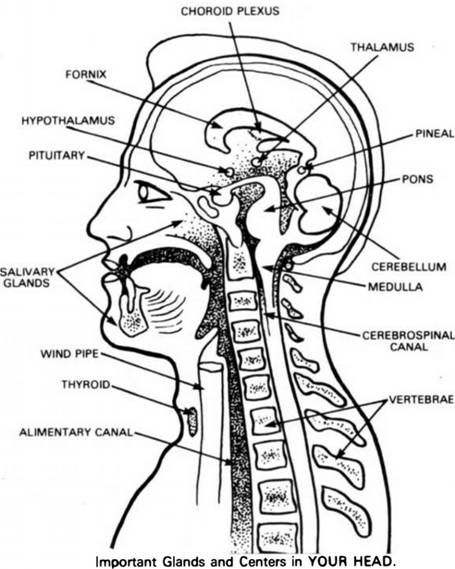

It is my opinion that the most important subject missing in elementary schools, is ANATOMY. This sketch is included here to serve as a guide and handy reference. The numbers indicate the location of the various parts.

1. The Frontal Sinus, in the forehead, above the eye where mucus accumulates eventually when we eat excessive amounts of concentrated starches, and drink too much milk.

2. The Pituitary Gland (or Body) is located directly behind and just a little below the level of the bridge of the nose.

3. The Pineal Gland, located in the mid-brain, back, and slightly higher than the Pituitary.

4. The Tongue, one of the most mischievous organs of the human body.

5. The Medulla Oblongata, the central Nerve-telephone-exchange, is situated in the lower middle part of the head between the upper lip and the base of the skull, just above the Atlas or first cervical vertebra.

6. The Parotid Gland, which becomes swollen and causes Mumps, especially when children and adolescents indulge in excesses of starches and candies.

7. The Sub-Lingual Gland.

8. Sub-Maxillary Gland.

9. The Epiglottis.

10. The Pharynx

11. TheThyroid Gland, one of the most vital and important glands of the body. It requires Iodine-foods for proper functioning. When improperly nourished causes Goiter.

12. The Larynx.